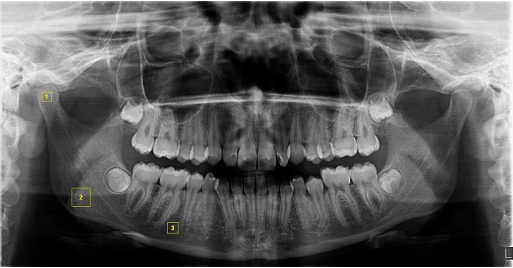

Region of interest (ROI) was selected bilaterally with dimensions of 50x50 pixels in the mandibular condyle, 100x100 pixels in the angulus, and 60x60 pixels in the corpus (between the second premolar and first molar) as shown in Figure 1. After the duplication of each ROI (Figure 2a), one copy was blurred using the Gaussian filter (sigma=35 pixels) (Figure 2b). The resulting image was removed from the original (Figure 2c), and 128 shades of gray were added for each pixel location (Figure 2d). Every image was changed to an 8-bit format. Then, the trabecular and bone marrow outlines were identified with the “Threshold” tab (Figure 2e). The noise was reduced using the “Erode” tab (Figure 2f), and then structures were made visible using the “Dilate” tab (Figure 2g). The “Invert” tab was used to turn the black areas white and vice versa (Figure 2h). As necessary lines for fractal analysis, the trabecular skeleton outlines were displayed using the “Skeletonize” tab (Figure 2i). Finally, the image was divided into squares of 2,3,4,6,8,12,16,32,64 pixels with the “Fractal box counting” under the “Analyze” tab, and the fractal dimension (FD) value was calculated. The same steps were applied for each panoramic radiograph. After one month, half of the randomly selected radiographs were secondly examined by the same researcher to assess the measurement reliability.

Figure 1. Determination of the regions of interest (ROIs) on the panoramic radiography. The yellow squares indicate the ROIs; 1, mandibular condyle region (50 x 50); 2, mandibular angulus region (100 x 100); 3, mandibular corpus region (60 x 60)